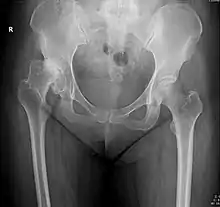

X-ray of hip dysplasia

X-rays of hip dysplasia are one of the two main methods of medical imaging to diagnose hip dysplasia, the other one being medical ultrasonography.[1][2] Ultrasound imaging yields better results defining the anatomy until the cartilage is ossified. When the infant is around 3 months old a clear roentgenographic image can be achieved. Unfortunately the time the joint gives a good x-ray image is also the point at which nonsurgical treatment methods cease to give good results.